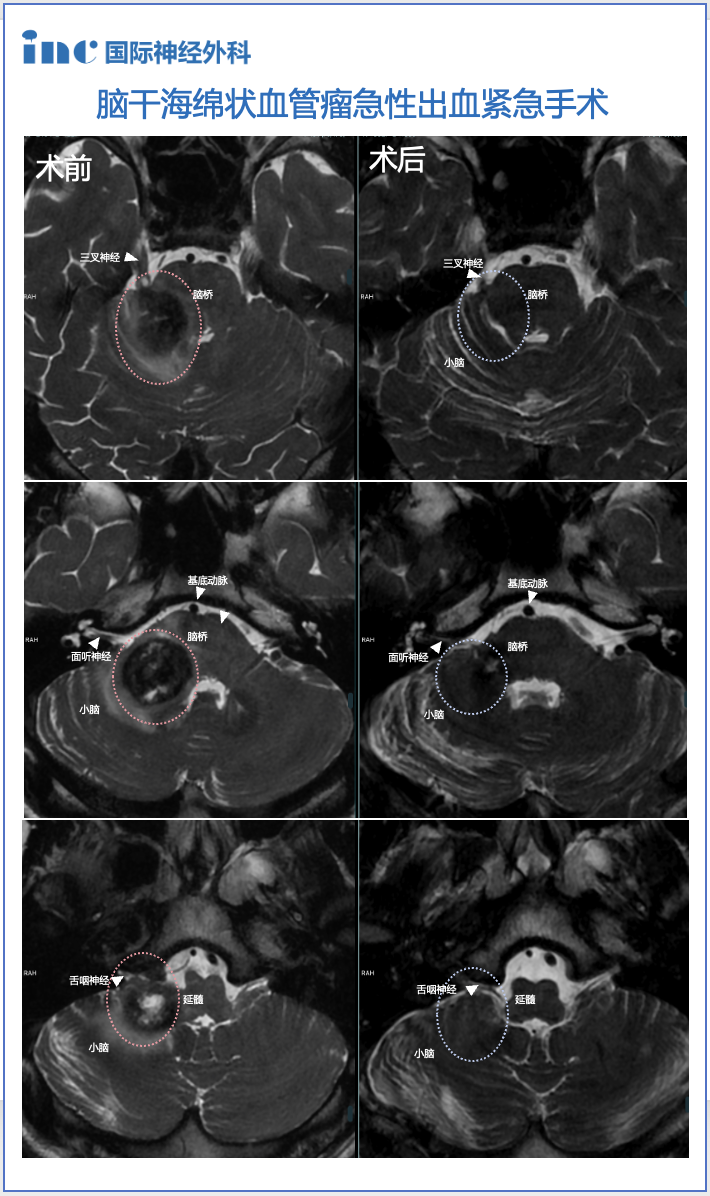

术前情况:20岁,大学生,意识紊乱并逐渐恶化,左偏瘫,MRI显示脑干中脑出血,急性梗阻性脑积水。病变位于脑干腹侧中脑中线,体积为10.7立方毫米,深度为42.5mm和和11.6°的肿瘤侧倾角(图A、B)。

手术入路:巴特朗菲教授根据患者的病情和肿瘤生长及MRI影像特点,先行脑室引流术,后采用双额骨瓣开颅、经基底纵裂入路进行病变全切手术。

术后情况:术后Maritta的恢复也很顺利。患者的意识和偏瘫迅速改善,脑积水消退。病人步行出院,没有3个月后随访的神经或认知功能障碍。术后MRI显示完全切除了轴内血肿和血管病变(图C、D)。

图A和B显示术前MRI影像,出血性中脑海绵状血管瘤诊断明确。黄色虚线表示肿瘤深度(42.5毫米)。图C、D显示完全切除血管病变后的术后MRI,病变全切,压迫占位效应解除,脑组织复位,未见手术损伤如脑出血、脑水肿等。